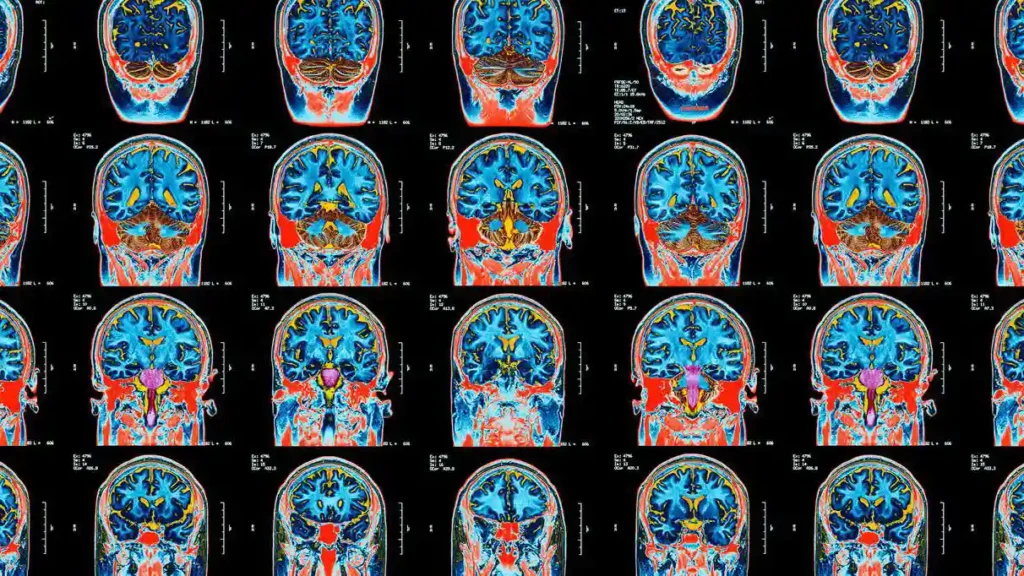

AI analysis of MRI data can accurately identify changes that result from repeated head injury, with potential to help illuminate how subtle brain injuries accumulate over time.

An interdepartmental collaboration at NYU Langone creates a vast shared repository of MR images to help advance the scientific understanding of metastatic brain cancer.